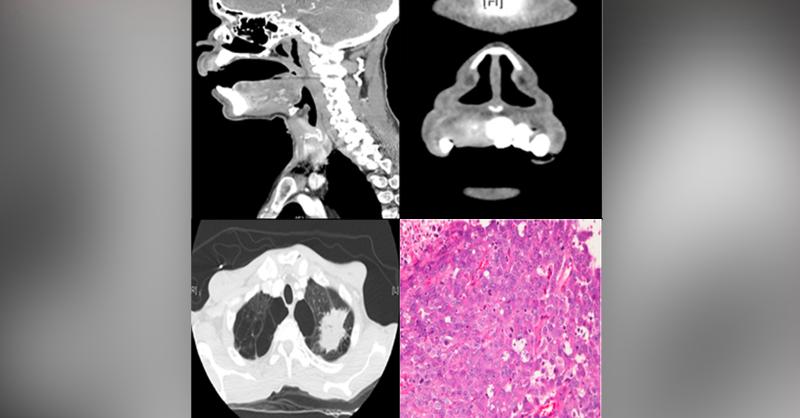

A 58-year-old male presented with a 2 month history of "dental abscess". He was also treated with tooth extractions and antibiotic therapy prior to the presentation, but his dental abscess persisted. His tobacco smoking history is a 10-pack-years. The patient reported bilateral neck swelling, exertional dyspnea, a 35-pound weight loss, and severe r